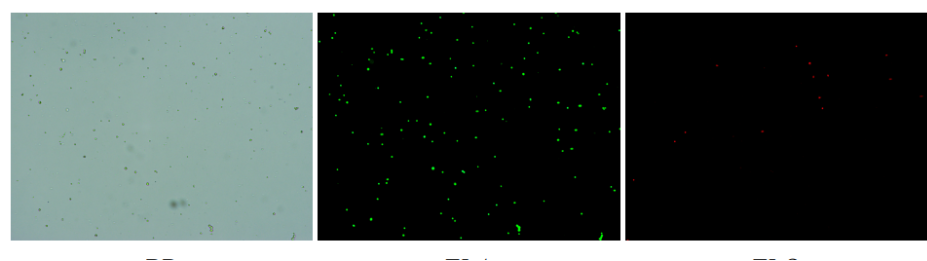

肝臟是人體代謝和解讀的器官,在體內發揮氧化、儲存肝糖、合成分泌性蛋白合成等,肝臟也制造消化系統中之膽汁,人肝約有25億個肝細胞。但是解離肝臟組織懸液并不簡單,首先,肝臟代謝旺盛,離體后肝細胞無法進行正常的有氧糖酵解,細胞活力會迅速下降,另外,肝細胞的線粒體很多,每個細胞大約有1000個左右,遍布于胞質內。因此,很難得到符合單細胞測序要求的單細胞懸液。百邁客生物在肝臟組織單細胞懸液制備方面有豐度的實操經驗,開發了獨有的解離體系,下面來看實驗結果:

實驗結果

人膽管癌樣本,活性90.45%,結團率7.2%

Tips: 肝實質細胞經過解離后因為缺氧非常容易發生凋亡,導致占比很低,如果老師關注肝實質細胞的話,建議采用單細胞核懸液的方法。